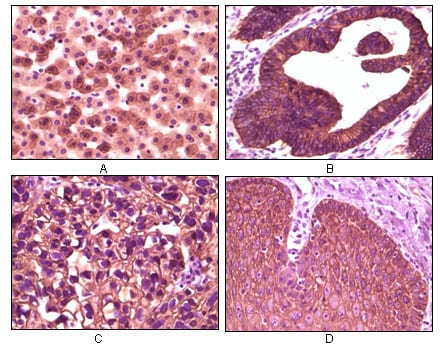

分类: 科研抗体货号: 20059别名: BFGF; FGFB; HBGF-2; FGF2应用: IHC反应种属: Human

分类: 科研抗体货号: 20073别名: HTK; MYK1; TYRO11应用: IHC反应种属: Human

分类: 科研抗体货号: 20054别名: S100A6; 2A9; PRA; 5B10; CABP; CACY应用: IHC反应种属: Human

分类: 科研抗体货号: 20071别名: ECK; EPHA2应用: WB,IHC反应种属: Human

分类: 科研抗体货号: 20088别名: K1; CK1; EHK; EHK1; EPPK; KRT1A; NEPPK应用: IHC反应种属: Human

分类: 科研抗体货号: 20069别名: APP应用: IHC反应种属: Human